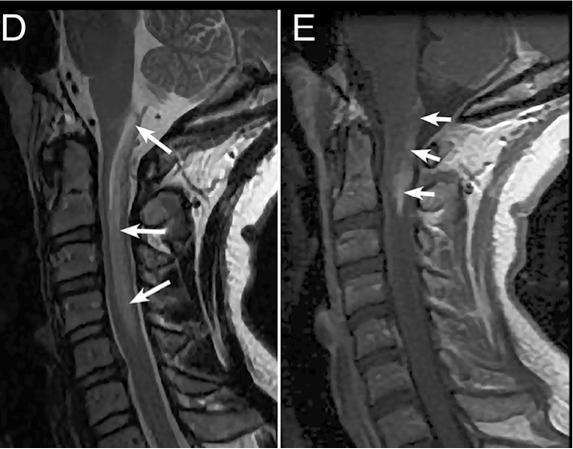

二、影像特征 1. NMOSD 脊髓MRI:长节段的脊髓炎(≥3个节段),呈中心分布,横贯性